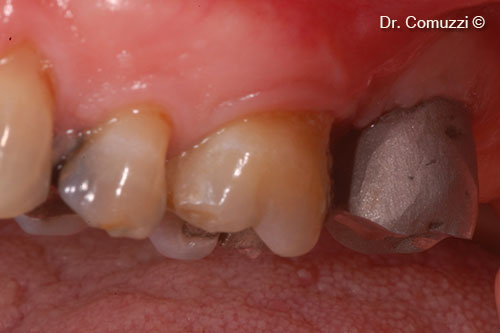

1. Initial clinical situation: 27 is missing